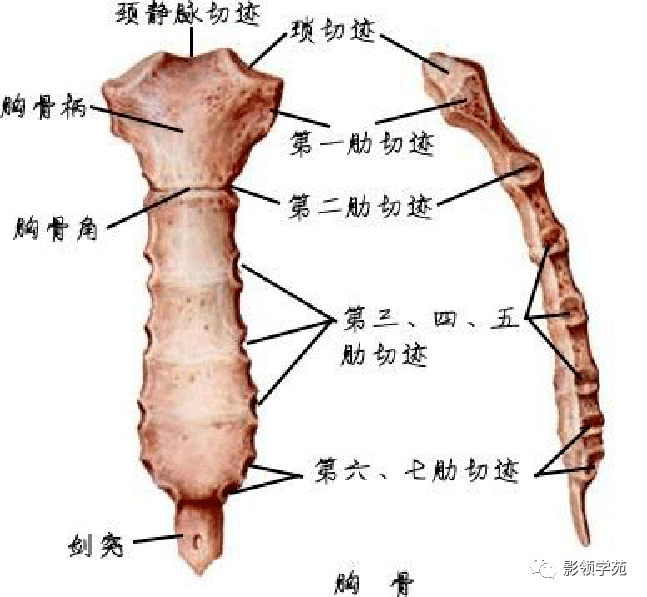

骨骼系统

骨骼系统